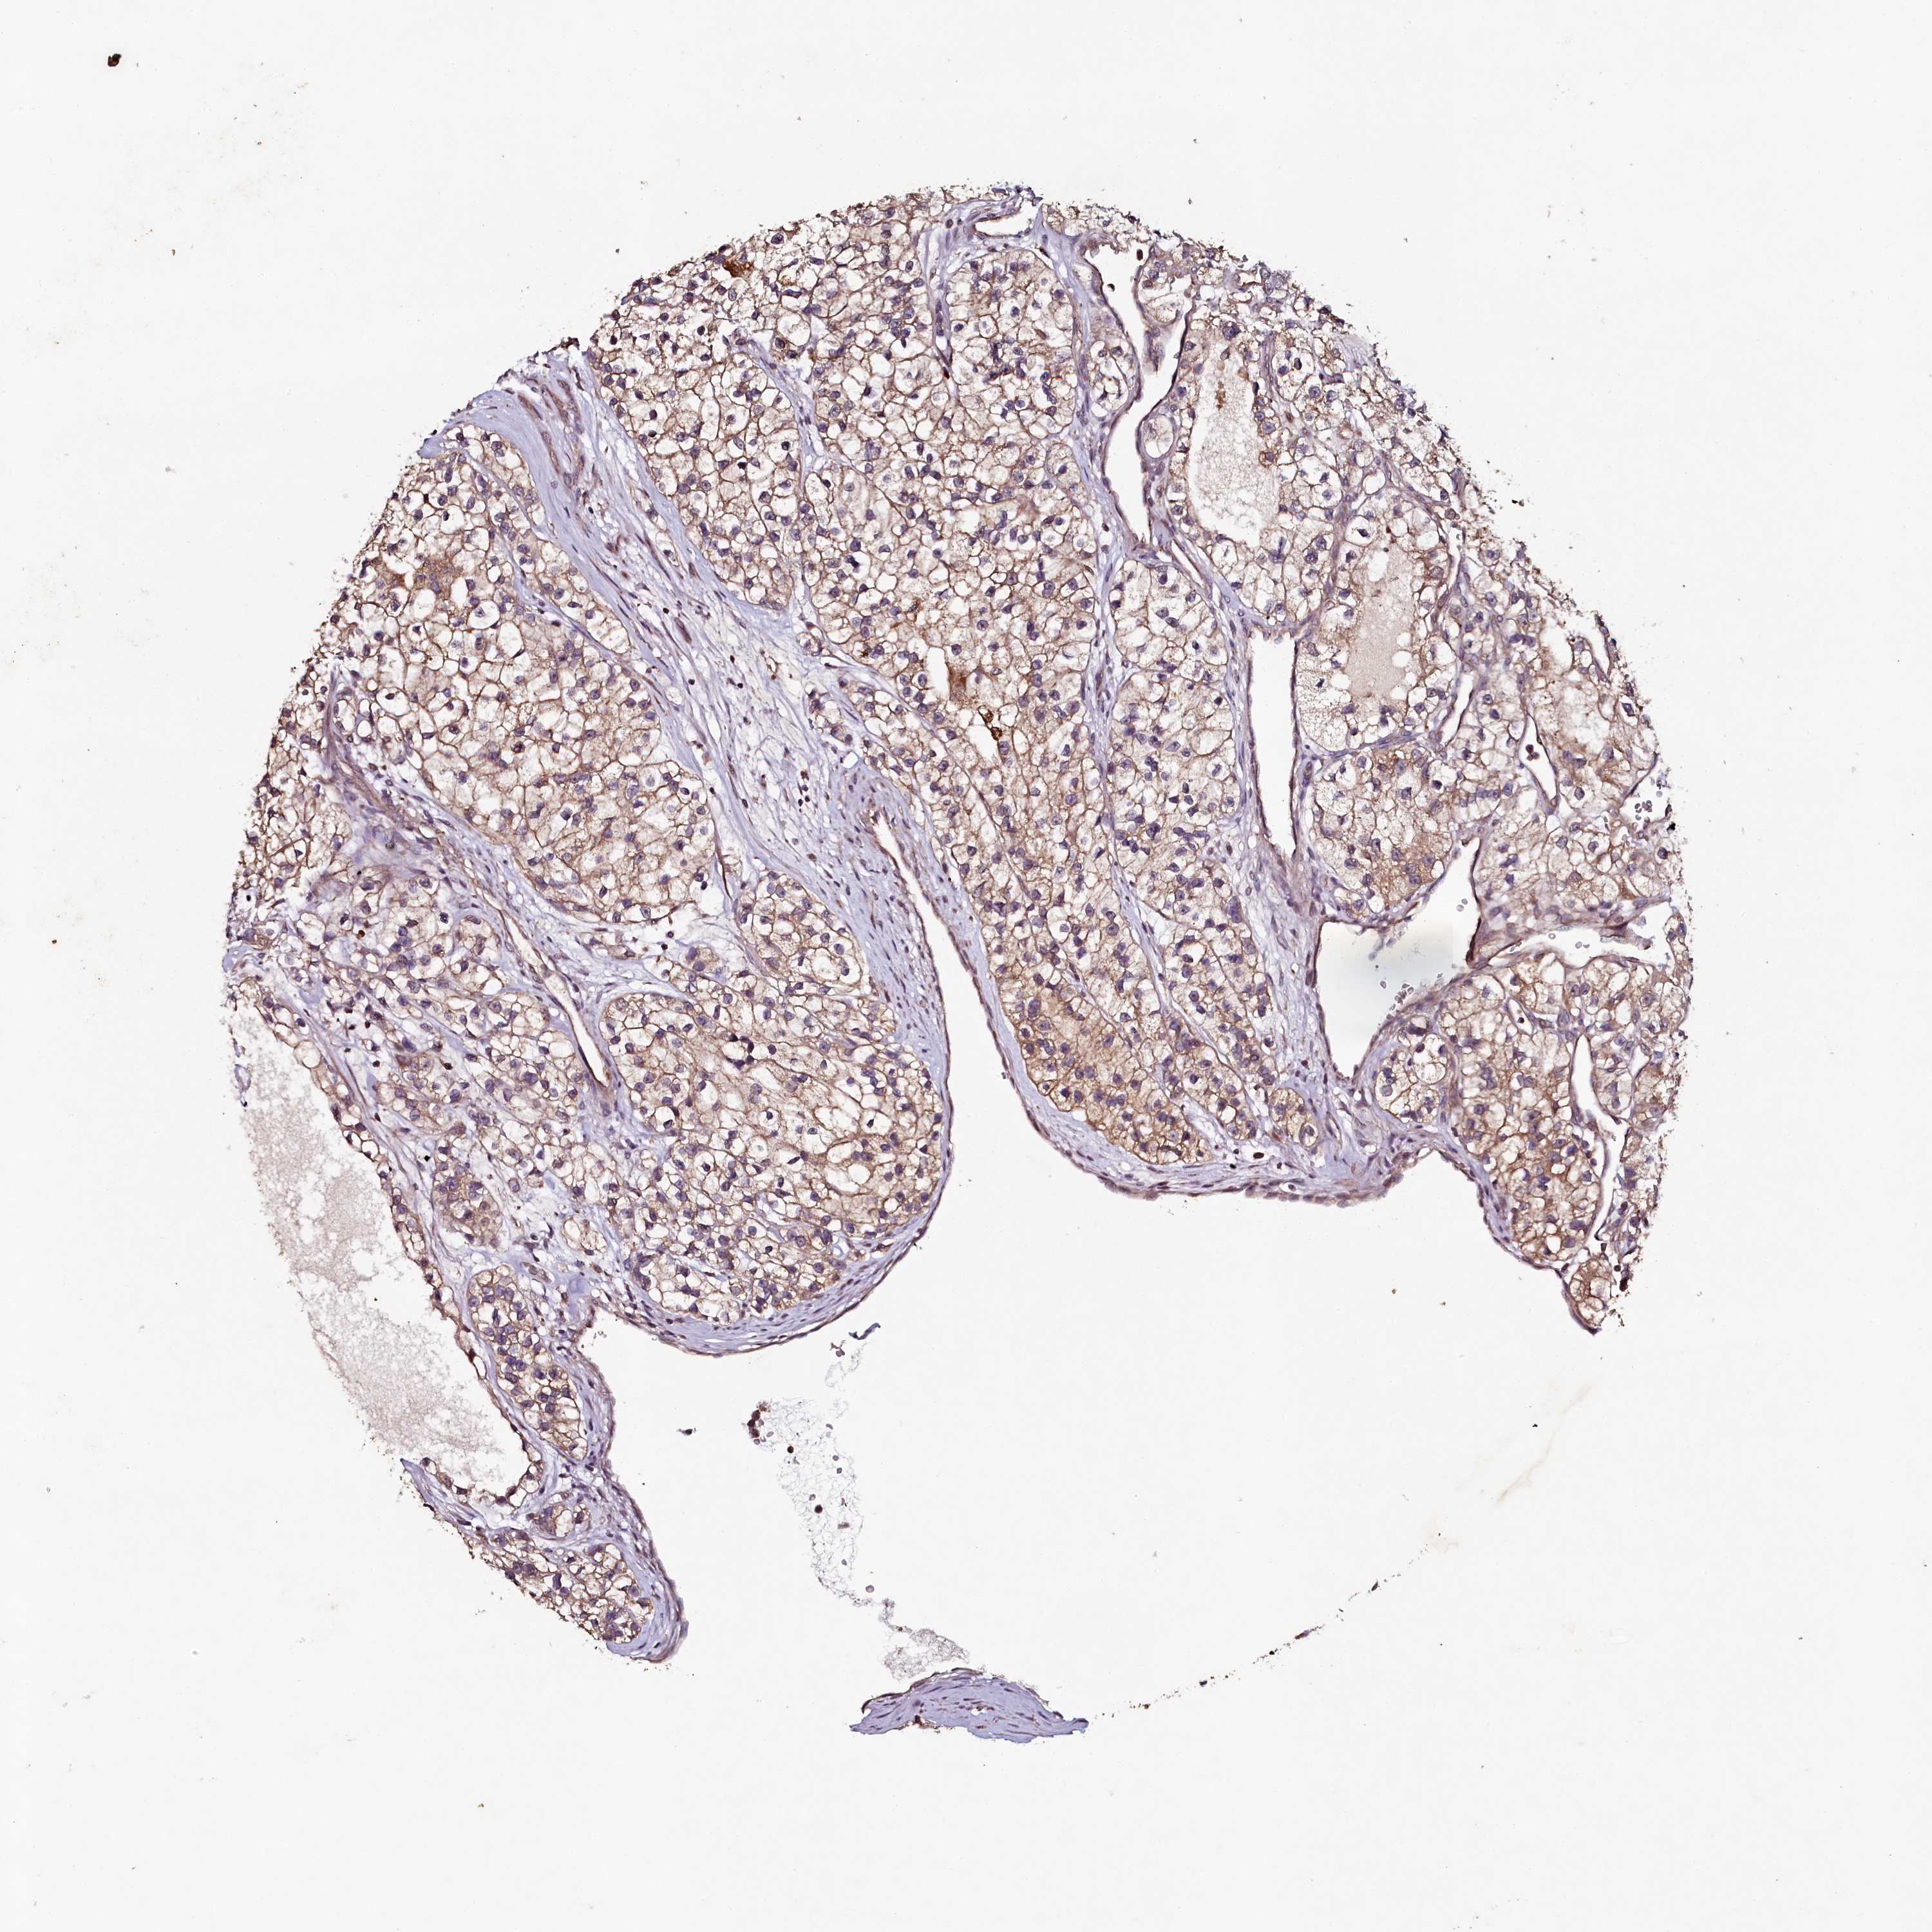

KIDNEY RENAL CLEAR CELL CARCINOMA (VALIDATION) - Interactive survival scatter ploti

The Survival Scatter plot shows the clinical status (i.e. dead or alive) for all individuals in the patient cohort, based on the same data that underlies the corresponding Kaplan-Meier plots. Patients that are alive at last time for follow-up are shown in blue and patients who have died during the study are shown in red.

The x-axis shows the expression levels (FPKM) of the investigated gene in the tumor tissue at the time of diagnosis. The y-axis shows the follow-up time after diagnosis (years). Both axes are complimented with kernel density curves demonstrating the data density over the axes. The top density plot shows the expression levels (FPKM) distribution among dead (red) and alive patients (blue). The right density plot shows the data density of the survived years of dead patients with high and low expression levels respectively, stratified using the cutoff indicated by the vertical dashed line through the Survival Scatter plot. This cutoff is automatically defined based on the FPKM cutoff that minimizes the p-score. The cutoff can be changed by dragging the vertical line or by entering a cutoff value in the square labeled "Current cut-off".

Under the Survival Scatter plot the p-score landscape (black curve; left axis) is shown together with dead median separation (red curve; right axis). Dead median separation is the difference in median mRNA expression between patients who have died with high and low expression, respectively. It is calculated as follows: median FPKM expression of dead patients with high expression - median FPKM expression of dead patients with low expression. This is intended to aid the user in visually exploring custom cutoffs and the associated p-scores and dead median separation.

Individual patient data is displayed and can be filtered by clicking on one or more of the category buttons on the top of the page. Categories describing expression level and patient information include: high, low, alive, dead, female, male and tumor stages. The scale of the x-axis can be toggled between linear and log-scale by clicking on the "x log" button. Mouse-over function shows TCGA ID, patient information and mRNA expression (FPKM) for each patient.

& Survival analysisi

Kaplan-Meier plots summarize results from analysis of correlation between mRNA expression level and patient survival. Patients were divided based on level of expression into one of the two groups "low" (under cut off) or "high" (over cut off). X-axis shows time for survival (years) and y-axis shows the probability of survival, where 1.0 corresponds to 100 percent.

SEC24C is not prognostic in Kidney Renal Clear Cell Carcinoma (validation)

Best expression cut offi

Based on the FPKM value of each gene, patients were classified into two groups and association between prognosis (survival) and gene expression (FPKM) was examined. The best expression cut-off refers the FPKM value that yields maximal difference with regard to survival between the two groups at the lowest log-rank P-value. Best expression cut-off was selected based on survival analysis .

When clicking on this number, the vertical dashed line indicating cut-off, the interactive survival plot, and the Kaplan-Meier curve will be adjusted to show results based on the best expression cut-off.

: 44.65

TCGA RNA samplesi

RNA-seq data is reported as average FPKM (number Fragments Per Kilobase of exon per Million reads), generated by the The Cancer Genome Atlas (TCGA) .

Normal distribution across the dataset is visualized with box plots, shown as median and 25th and 75th percentiles. Points are displayed as outliers if they are above or below 1.5 times the interquartile range. FPKM values of the individual samples are presented next to the box plot.

Average pTPM 42.4

Number of samples 100